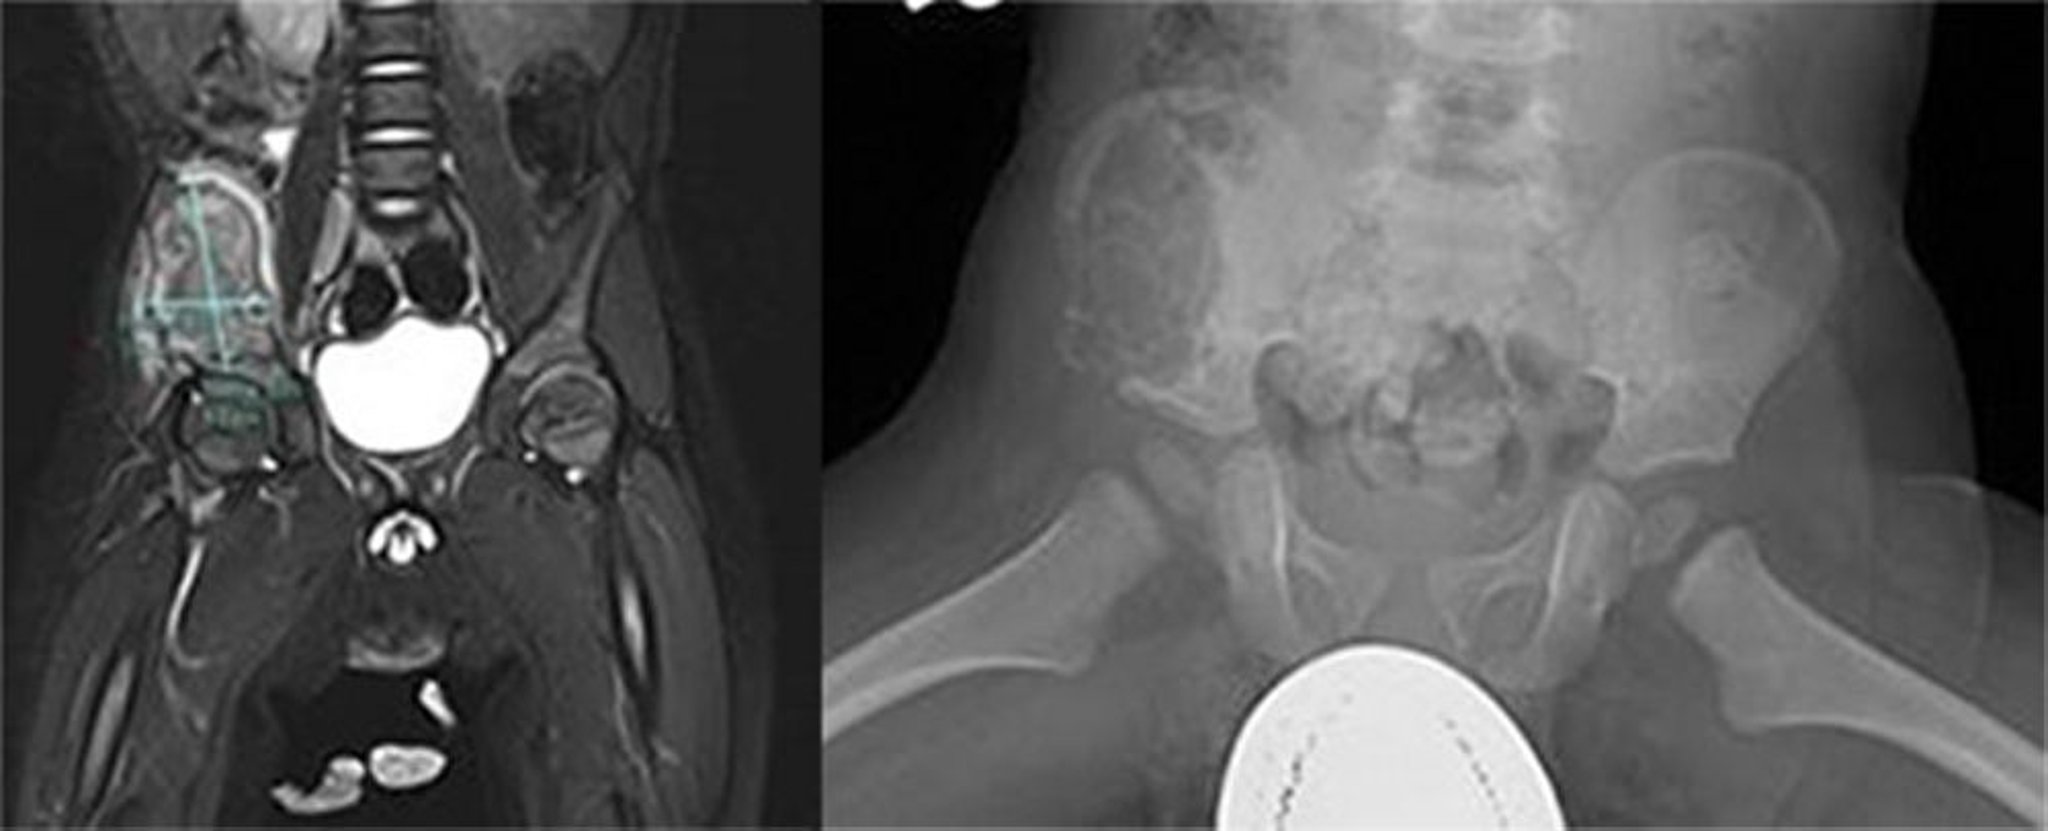

Langerhans-Zell-Histiozytose (Beckenknochen)

Dieses Bild zeigt eine große aggressive Läsion im rechten Darmbeinflügel. Eine MRT-Untersuchung ergab eine heterogene T2-Masse und ein schwaches T1-Signal mit heterogener Anreicherung der Masse und der umgebenden Muskulatur mit einer Abweichung des rechten Psoas-Muskels nach medial, was auf eine aggressive Knochenläsion hindeutet (links). Auf dem Röntgenbild war eine große lytische Läsion im vorderen und lateralen Bereich des Ileums zu erkennen, die sich nach vorne und nach unter bis zum Sitzbein erstreckte (rechts). Es gibt einen erweiterten Kortex und kortikale Unregelmäßigkeiten. Die Biopsie war diagnostisch für Langerhans-Zell-Histiozytose.

Images courtesy of Carolyn Fein Levy, MD, and Jeffrey M. Lipton, MD, PhD.